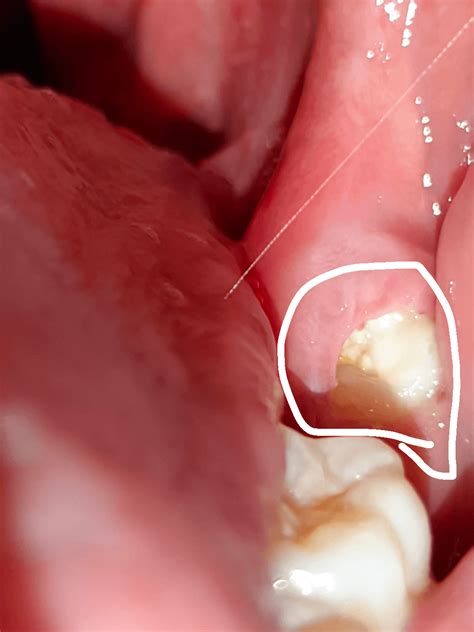

Discovering a black dot inside cheek can be a startling experience that often triggers immediate concern about oral health. While it is natural to worry about potential underlying conditions, these spots are frequently benign and may result from simple causes like accidental trauma or pigmentation. However, because the oral cavity is complex, it is essential to understand what these spots could signify and when professional intervention becomes necessary. This comprehensive guide will walk you through the potential causes, common symptoms, and the importance of professional dental evaluation.

The mouth is a highly vascular area, and the lining of the cheeks (the buccal mucosa) is susceptible to various changes. A black dot inside cheek can appear due to several factors, ranging from harmless physical injuries to more complex dermatological or systemic issues. Identifying the nature of the spot often depends on its size, texture, duration, and whether it is accompanied by pain or other symptoms.

When you notice a dark spot, it is helpful to consider recent history: have you recently bitten your cheek? Is there a history of tobacco use? Have you started any new medications? These questions help in narrowing down the possibilities before a dentist or doctor conducts a formal examination.

One of the most common reasons for a sudden black dot inside cheek is an accidental bite. If you bite the inside of your cheek while eating, a small blood vessel may rupture, creating a localized hematoma. This appears as a dark red, purple, or black spot. It usually heals on its own within a week or two.

If you have silver (amalgam) dental fillings, a small piece of the metal can sometimes become embedded in the soft tissue during the filling process or when the tooth is polished. This creates a flat, bluish-black or grey spot that is permanent but completely harmless. It does not grow or change over time.

Similar to a freckle on the skin, an oral melanotic macule is a flat, brown to black patch of increased melanin. These are common, benign, and typically do not require treatment. They are usually found on the lips or the lining of the cheeks.

While significantly less common, any persistent dark spot in the mouth should be evaluated to rule out oral cancer, particularly melanoma, which can occur in the mouth. These spots might be irregular in shape, change color, grow in size, or bleed.

⚠️ Note: If a spot has been present for more than two weeks and does not show signs of healing, do not wait. Schedule an appointment with your dentist or an oral pathologist for an evaluation.